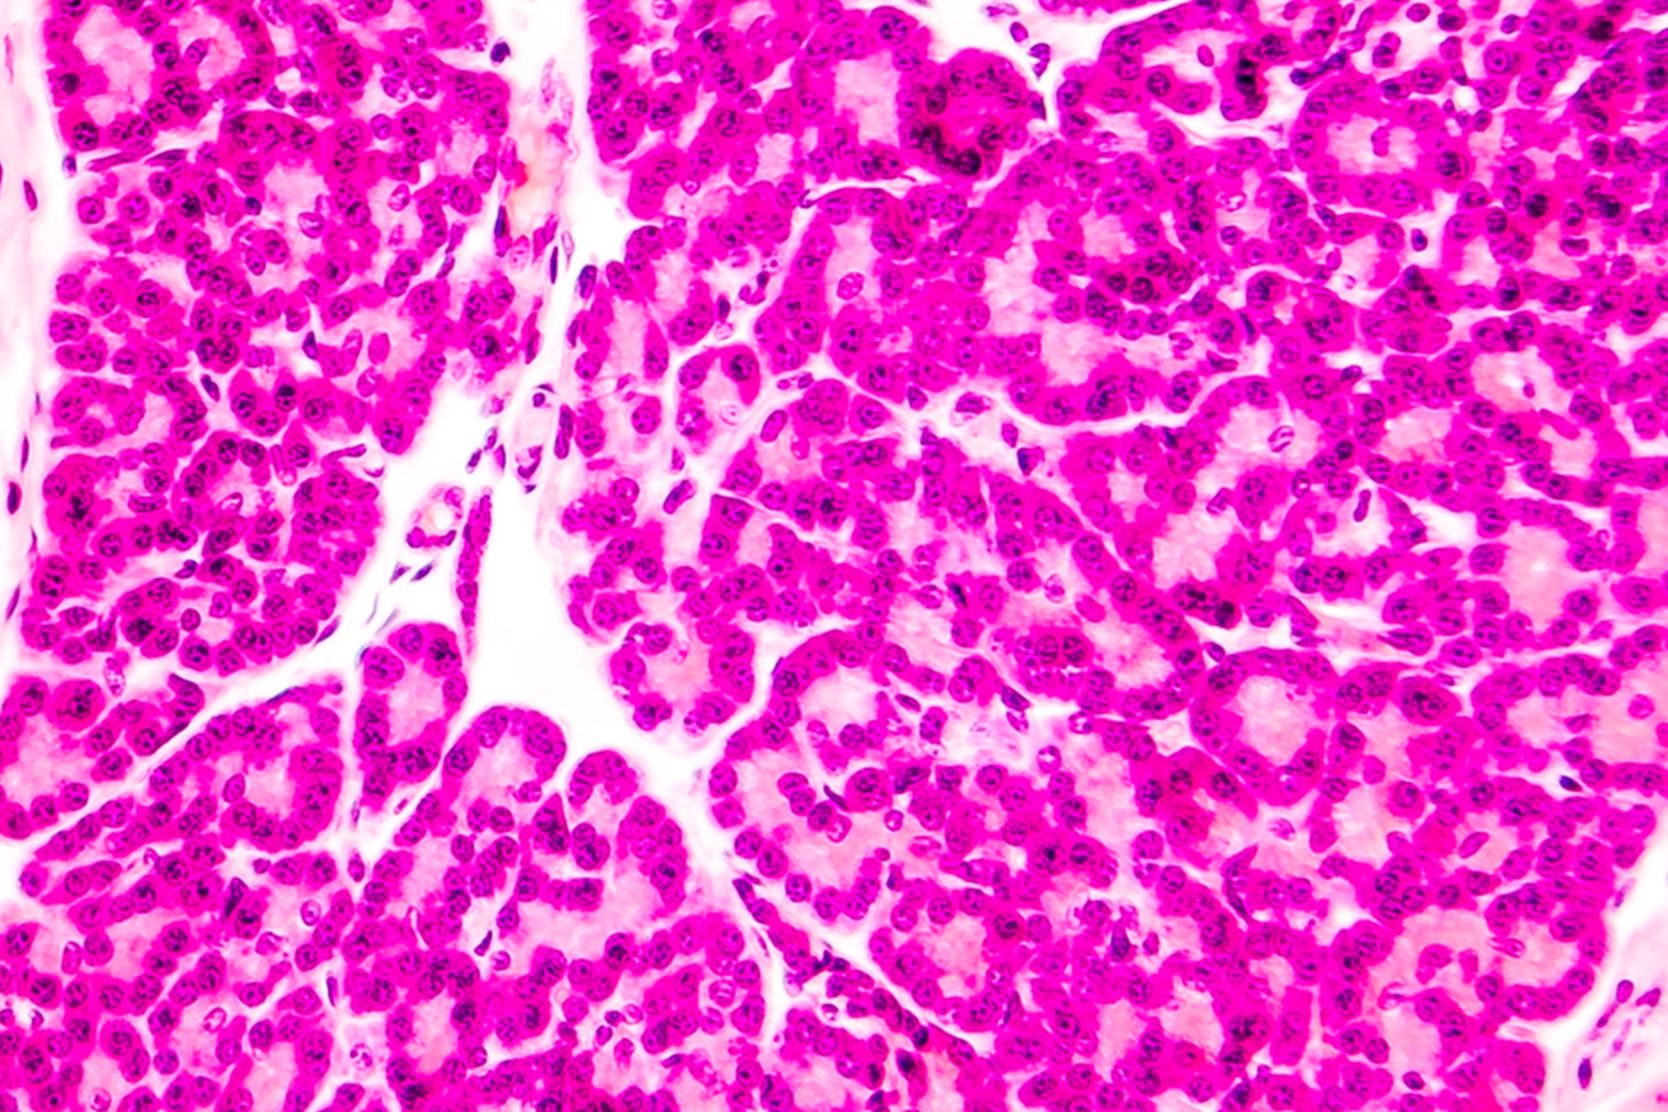

Type 1 diabetes. About 5 to 10 percent of those with diabetes have type 1 diabetes. It's an autoimmune disease, meaning the body's own immune system mistakenly attacks and destroys the insulin-producing cells in the pancreas. Patients with type 1 diabetes have very little or no insulin, and must take insulin everyday. Although the condition can appear at any age, typically it's diagnosed in children and young adults, which is why it was previously called juvenile diabetes.